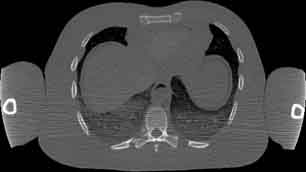

Visible Human male: Sectio transversalis 1477

CT

NMR

Pd                          / T2 \                         T1